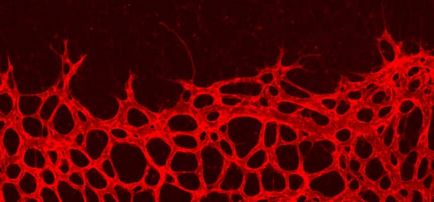

új kapillárisok

A tudósok kimutatták, hogy a rendszeres kitettség a hőt a kapillárisok lehetnek tízszer.

A tudósok kimutatták, hogy a rendszeres kitettség a hőt a kapillárisok lehetnek tízszer annyi, akkor nőni fog „vonat”. Ha a hajszálerek sokkal könnyebben hordozható és meleg, hideg. A veszteség a hajszálerek, amikor egyre kevésbé, az úgynevezett öregedés. Ha a szám a hajszálerek a bőrt, ráncossá válik, megereszkedett, száraz.

Még az AIDS-vírus, a HIV, a hepatitisz C kell semmisíteni, ha az általunk használt sok infravörös hő cautery módban. Ha a cél, hogy a vonat magát, és nőnek az új kapillárisok, felüdülést te és megszabadulni a baktériumok és fertőzések. Az onkológusok azt is igazolták, hogy az infravörös hő, a hatás miatt felhalmozása, egészségre vonatkozó egyes összegeket. Észrevettem, hogy miután 150-200 óra cauterizing vérnyomás csökkenni kezd fokozatosan, az emberek megszabadulni alkalmazásának szükségességét hegyi gyógyszerek.